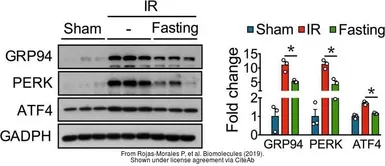

The data was published in the journal Biomolecules in 2019. PMID: 31505885

The data was published in the journal Biomolecules in 2019. PMID: 31443530

The data was published in the journal Biomolecules in 2019. PMID: 31443530

The data was published in the journal Biomolecules in 2019. PMID: 31443530

The data was published in the journal Biomolecules in 2019. PMID: 31443530

The data was published in the journal Biomolecules in 2019. PMID: 31443530

The data was published in the journal Biomolecules in 2019. PMID: 31443530